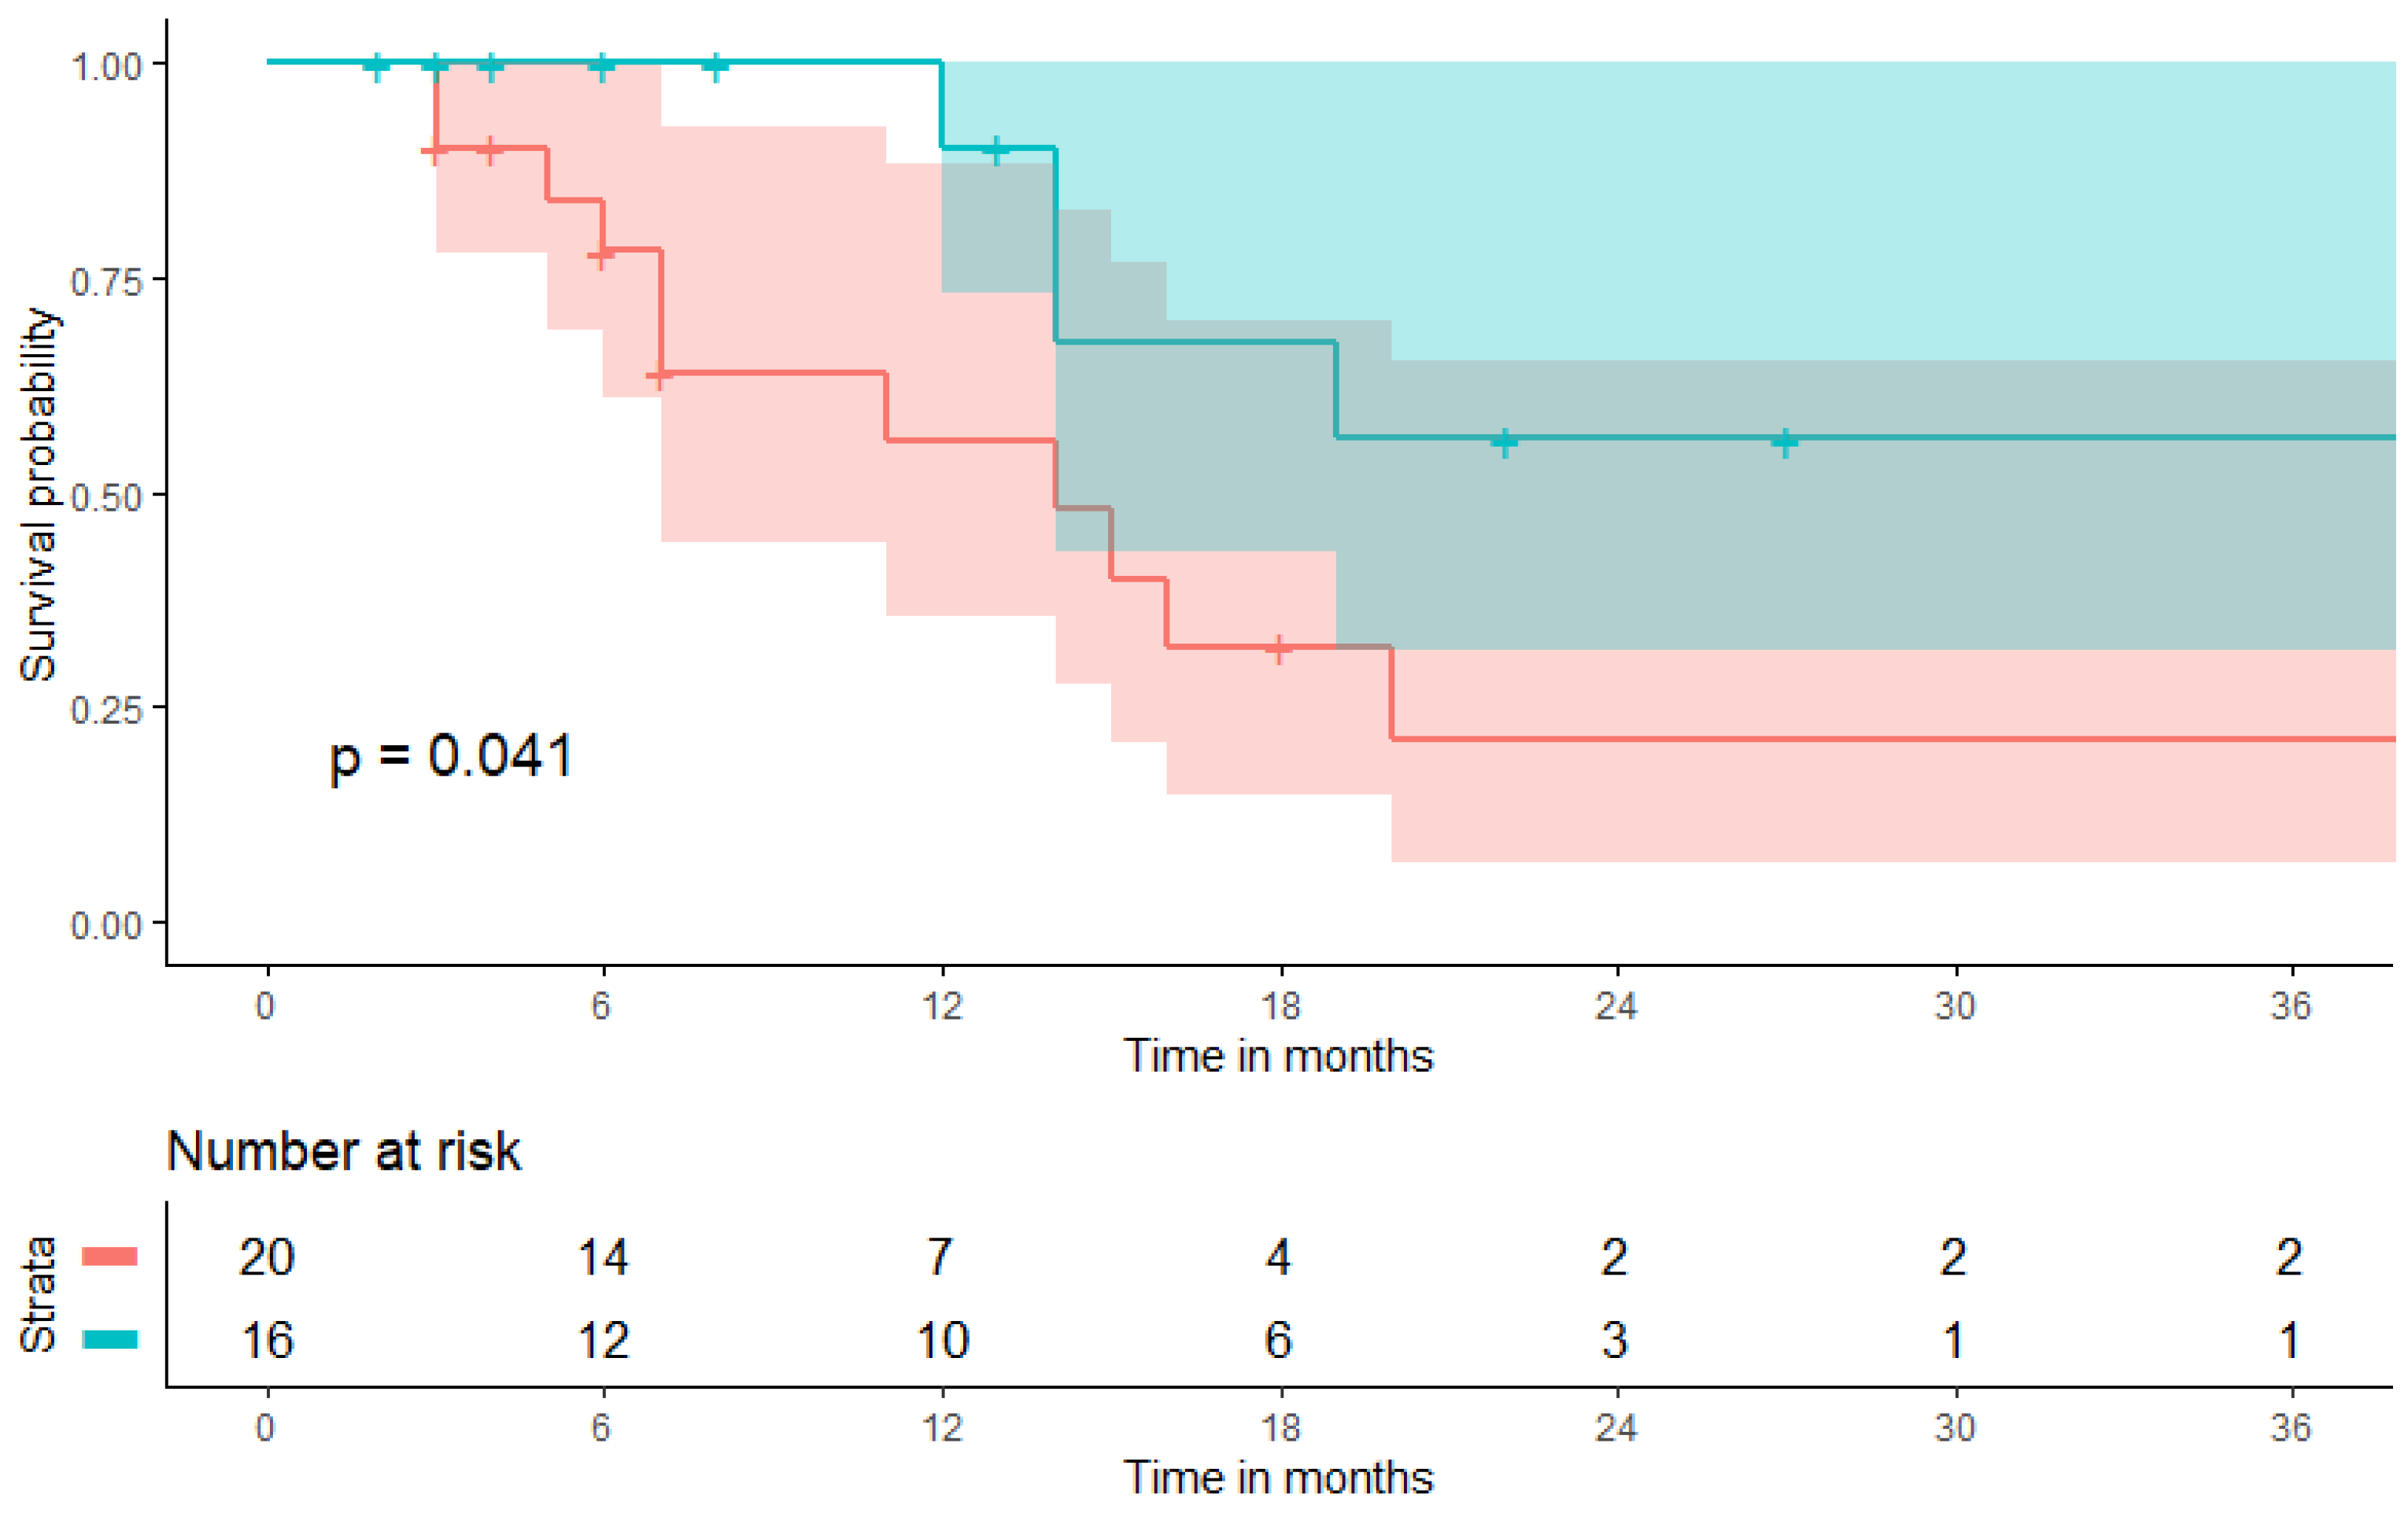

3.2. Predictive Value of a Pretherapeutic BMI for CPI Therapy

3.3. Prognostic Value of a Pretherapeutic BMI on Patient Survival during CPI Therapy

| progression-free survival (PFS, months) | 6.5 (3.0–13.8) | 4.0 (2.0–10.8) | 9.0 (4.0–20.5) | 0.102 * |

| overall survival (OS, months) | 9.5 (4.3–18.8) | 7.0 (4.3–15.8) | 13.5 (4.5–22.0) | 0.499 * |

| a. Parameters | PFS after CPI Therapy | |||

| Univariate Analysis | Multivariable Analysis | |||

| p-Value | OR (95% CI) | p-Value | OR (95% CI) | |

| combined positive score | 0.746 | 1.00 (0.99–1.01) | - | - |

| body mass index (5 kg/m2 increment) | 0.038 | 1.54 (1.03–2.34) | 0.002 | 3.73 (1.63–8.50) |

| neutrophile-to-lymphocyte ratio | 0.767 | 1.01 (0.95–1.08) | 0.789 | 0.99 (0.93–1.06) |

| age-adjusted charlson comorbidity index | 0.675 | 1.04 (0.85–1.28) | 0.419 | 1.11 (0.87–1.41) |

| subcutaneous fat volume (100 mL increment) | 0.992 | 1.00 (0.92–1.08) | 0.007 | 1.23 (1.06–1.43) |

| visceral fat volume (100 mL increment) | 0.487 | 0.95 (0.82–1.10) | - | - |

| b. Parameters | OS after CPI Therapy | |||

| Univariate Analysis | Multivariable Analysis | |||

| p-Value | OR (95% CI) | p-Value | OR (95% CI) | |

| combined positive score | 0.220 | 1.01 (0.991.–1.03) | - | - |

| body mass index (5 kg/m2 increment) | 0.028 | 1.87 (1.07–3.29) | 0.010 | 7.44 (1.62–34.16) |

| neutrophile-to-lymphocyte ratio | 0.397 | 1.04 (0.95–1.15) | 0.478 | 1.04 (0.94–1.14) |

| age-adjusted charlson comorbidity index | 0.959 | 0.99 (0.73–1.36) | 0.694 | 1.07 (0.75–1.53) |

| subcutaneous fat volume (100 mL increment) | 0.620 | 0.973 (0.873–1.08) | 0.035 | 1.36 (1.02–1.81) |

| visceral fat volume (100 mL increment) | 0.201 | 0.868 (0.70–1.08) | - | - |